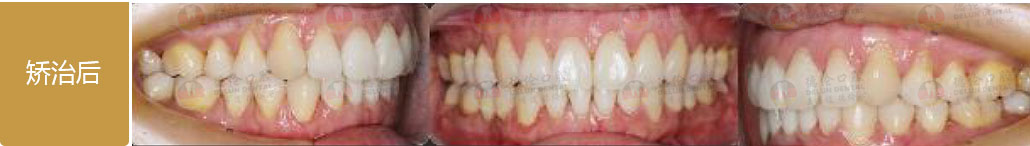

德倫口腔矯正診室指定專家團是以德倫口腔總院正畸科主任、時代天使全國智美隱形矯治病例大賽三等獎得主――熊小琴主任,和德倫口腔總院正畸科資深專家、隱形矯正培訓講師、有 26 年口腔醫療臨床經驗的王蘇靜醫生,共同領銜的 16 位隱形正畸認證醫師。指定專家團實力雄厚,臨床經驗豐富,內含多名口腔正畸專業博士、碩士組成的正畸博碩專家團和第 18 屆雅加達亞運會中國代表團時代天使口腔保障營專家團。